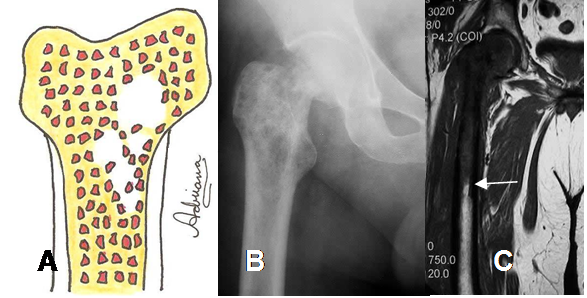

Fig 29. Lesión moteada.

A: Diagrama de lesión moteada, cuyos borde no son definidos.

B: Rx AP. Lesión de bordes mal definidos, en la cabeza femoral

C: RM coronal en T1. La lesión se extiende hasta la diáfisis del fémur, secundaria a osteosarcoma.